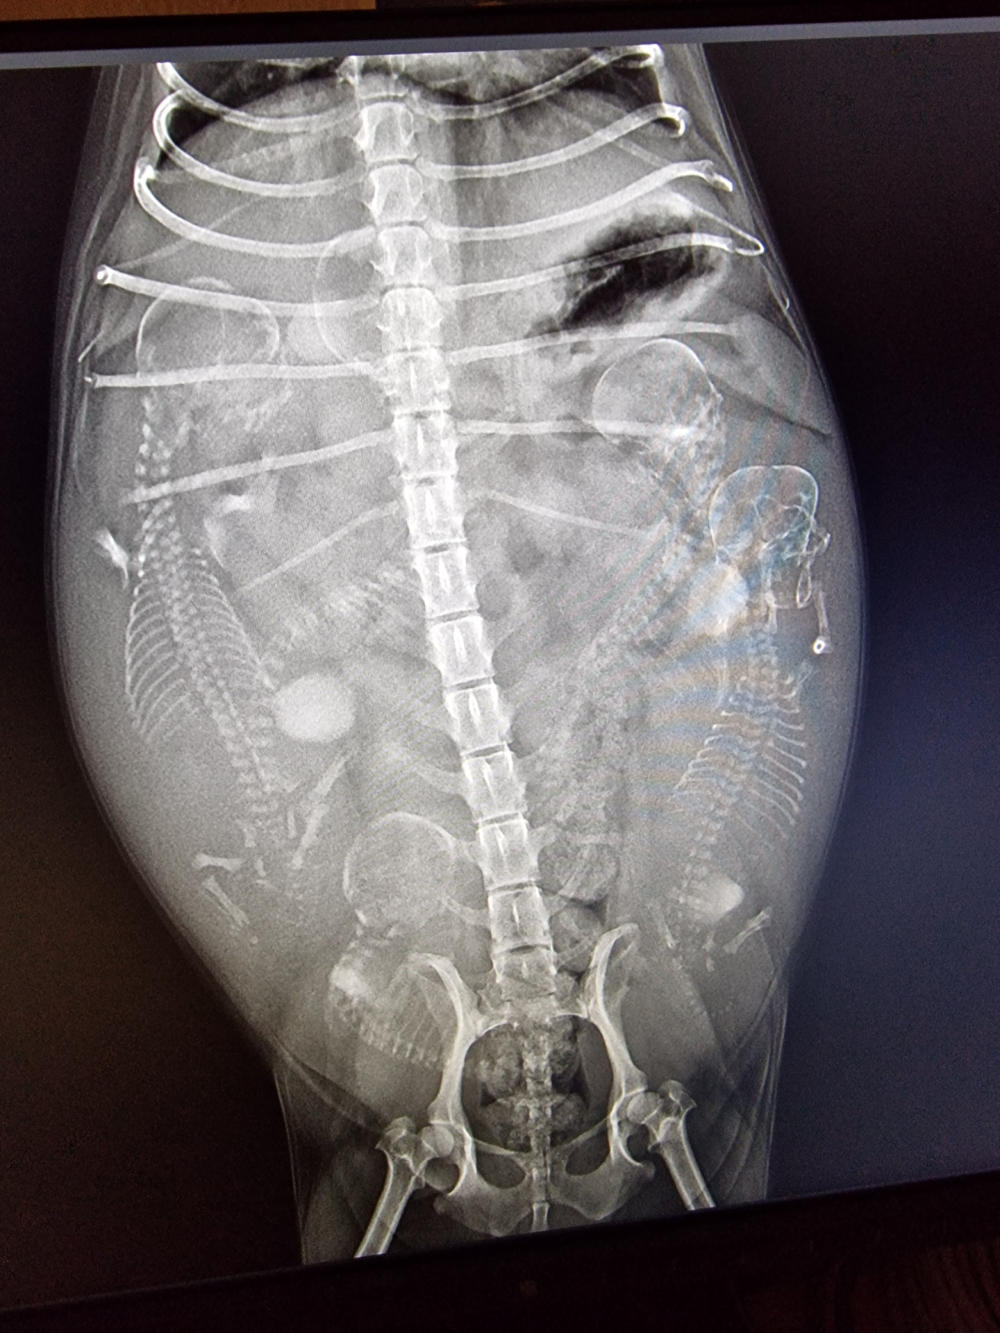

So, heute Morgen war unser Frauli auch mit den anderen drei Mädels zum Röntgen. Im Laufe der nächsten Woche kommt richtig Leben in unsere Bude. Hi, hi. (Röntgenbilder Yule, Lotta und Gina v.l.n.r.) Yule´s Welpen-Nestchen steht auch. Die von Lotta und Gina bauen unsere Niefi´s am Wochenende auf.